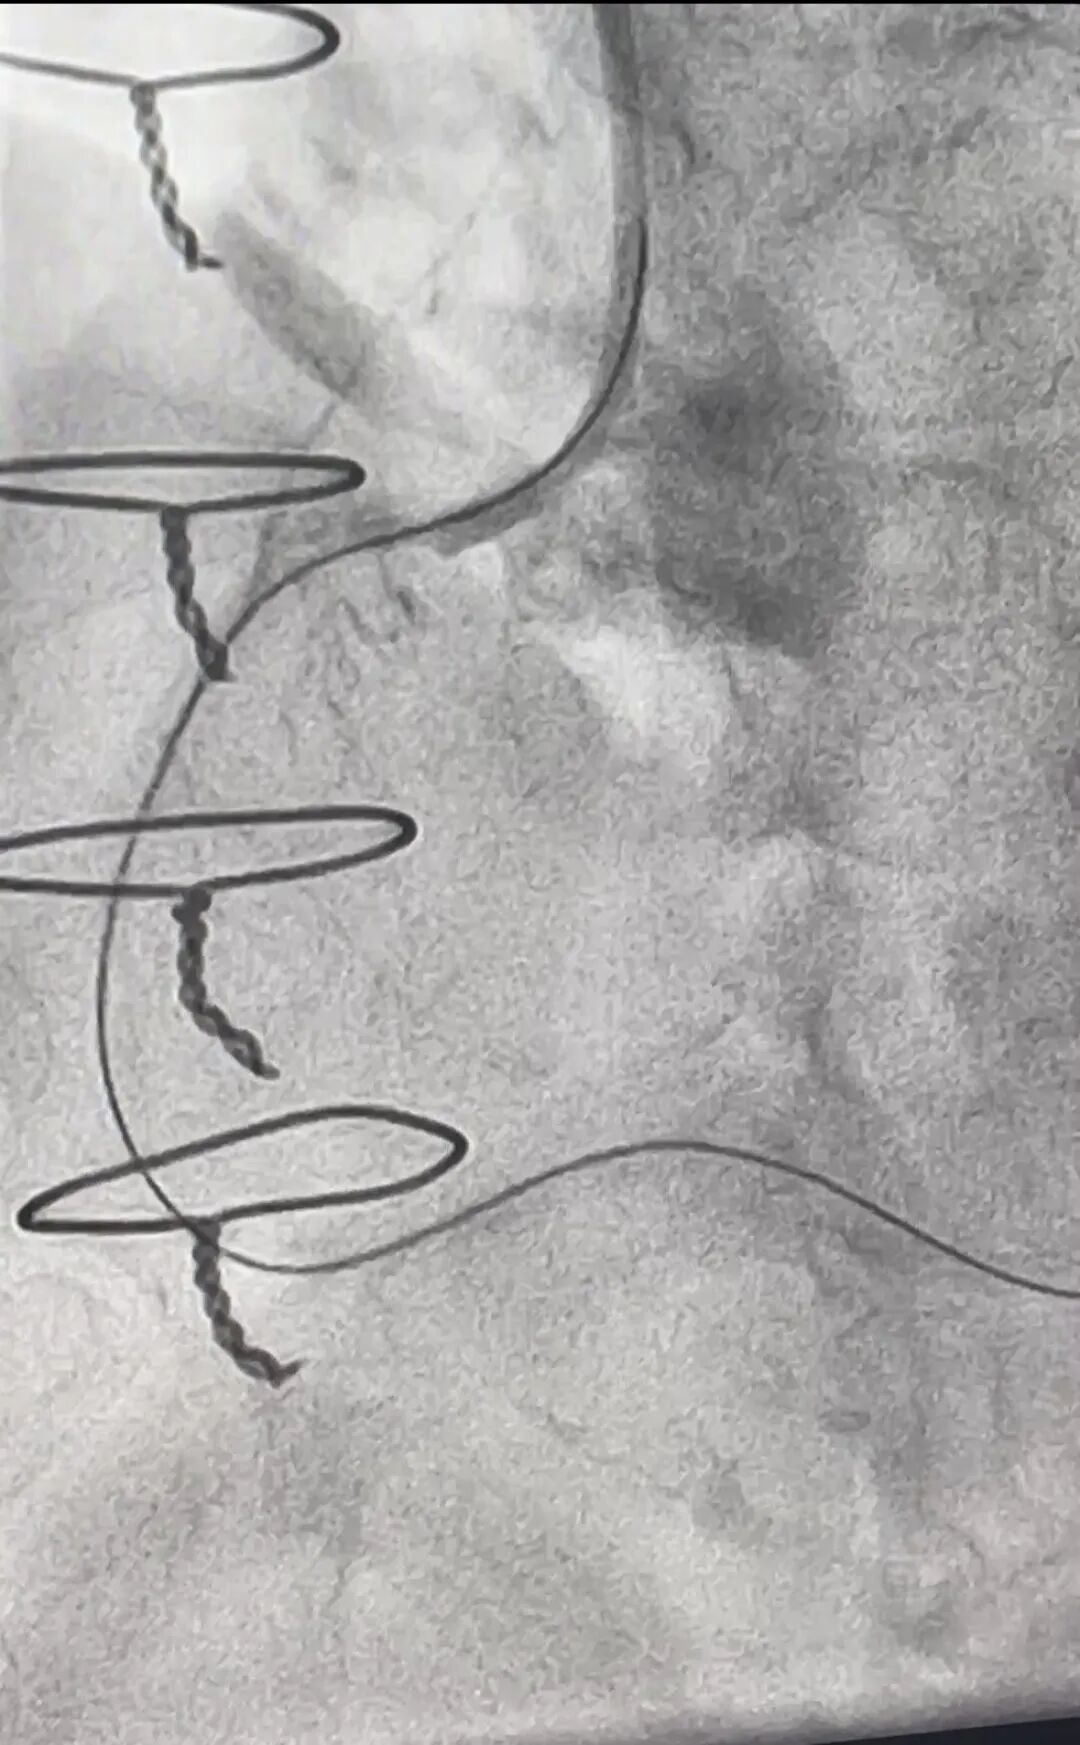

楼钶楠主任医师(右)正在实施手术

手术画面